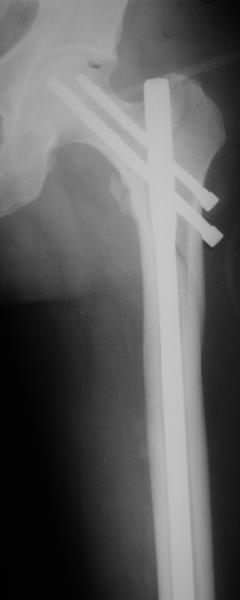

В диагноз пишем... Потом же как-то анализировать надо. Что-то никто не откликнулся на этот вопрос из англоязычных коллег. Все-таки - как такой перелом надо классифицировать? А если шейка бедра + диафиз? Завтра покажу такой случай.

Реконструкционный гвоздь.

Да, сейчас это и у нас самый напрашивающийся выбор. Сделали гвоздем ChM, картинки в приложении.

У молодых реконструкционный гвоздь самое то. При остеопорозе надо что-то помассивнее.